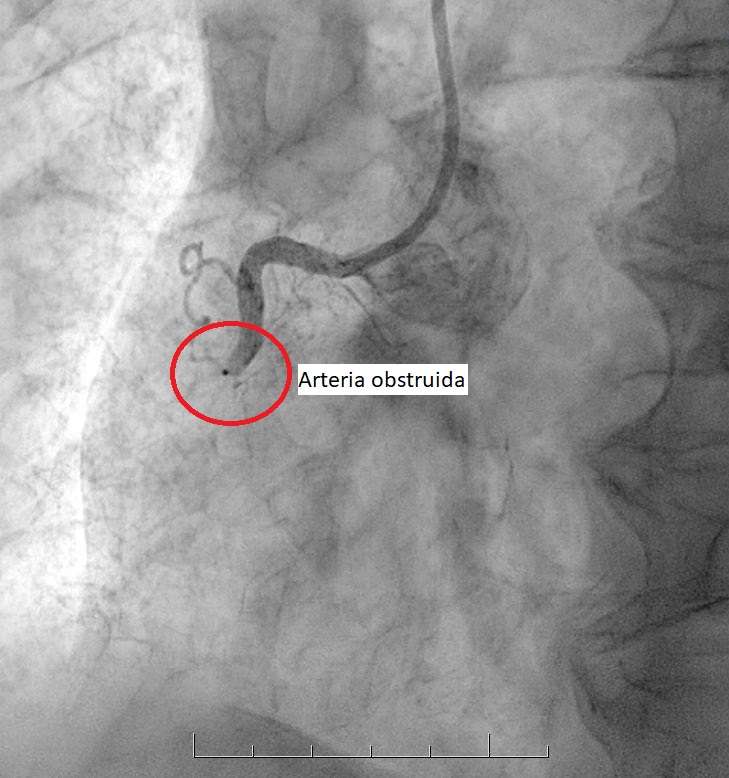

• Es un procedimiento que permite eliminar las obstrucciones de las arterias, abriendo el paso a la circulación de la sangre y dejando lugar para la colocación de un stent.

• La enfermedad coronaria se produce por la obstrucción de las arterias que llevan sangre al corazón. Para tratarla, existen tres métodos básicos: medicamentos, angioplastía o cirugía cardiovascular (by-pass).

• Es un pequeño tubo de malla metálica que, una vez ubicado en la arteria, se expande y queda adherido a sus paredes, reforzando el procedimiento de desobstrucción. Se utiliza, en la mayoría de los casos, como complemento de la angioplastía y da muy buenos resultados.

Este catéter llega hasta las arterias que se van a tratar y una vez allí se inyecta una sustancia de contraste, que permite visualizar las obstrucciones existentes. A través de este catéter se inserta un balón, que se expande en el sitio obstruido y luego se retira, dejando lugar para la colocación de un stent.